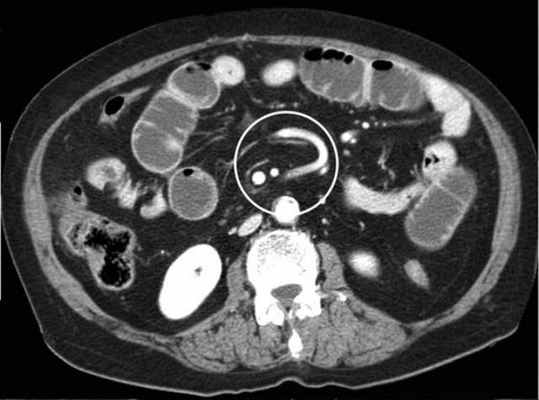

-Расширенные петли тонкой кишки проксимальнее транзиторной зоны (зоны обструкции).

-Под транзиторной зоной надо понимать зонy кишки с очевидной разностью в диаметре просвета между расширенным проксимальным сегментом и местом сужения/обструкции. Визуализация этой зоны зависит от причины и механизма обструкции, а также от проекции расположения петли (аксиально, фронтально и т.д.). К сожалению, обнаружение этой зоны не всегда представляется возможным. При спаечном механизме или воспалении многими хорошо описан признак "птичьего клюва". При обструкции в результате алиментарного болюса транзиторная зона будет выглядеть как гетерогенное образование в просвете кишки без признаков контрастного усиления.

-Спавшиеся петли кишечника дистальнее уровня обструкции.

-Смешанный характер стаза содержимого кишечника в расширенных петлях. Некоторыми авторами описан "фекалоидный" тип стаза, описанный в литературе как "каловое содержимое тонкой кишки", в английской литературе-“small-bowel faeces sign”. Патогенез данного признака включает в себя много факторов:

замедление пассажа содержимого, нарушения механизмов абсорбции и секреции в тонкой кишке, рефлюкс из толстой кишки из-за недостаточности илео-цекального клапана, постановка желудочного зонда. Необходимо помнить, что этот признак неспецифичен при тонкокишечной непроходимости, его также можно определить на УЗИ и обзорной рентгенограмме брюшной полости.

-Нормальные неутолщённые стенки кишечника с гомогенным одинаковым контрастным усилением.

-В тощей кишке рисунок ворсинок слизистой (valvulae conniventes) тонкий, и он одинаково выглядят на всём протяжении.

-Отсутствие патологических изменений толстой кишки, толстая кишка как правило спавшаяся или содержит небольшое количество калового содержимого, распределённого по всему просвету.

-Отсутствие воспалительных изменений в брыжейке и внутрибрюшинном жире.

-Нормальная васкуляризация сосудов брыжейки.

-Отсутствие свободной жидкости в брюшной полости.

Различные КТ сканы при простой форме обструкции, cxематично изображены транзиторные зоны и спайки, которые как "хомут" или "удавка" как-бы душат петлю кишки.

Значение реконструкций в разных проекциях для определения уровня обструкции.